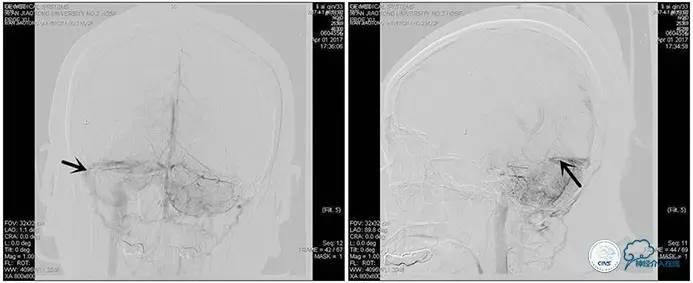

右侧ICA正位

右侧ICA侧位

右侧ICA斜位

左侧ICA正侧位

右侧VA正位

左侧VA正侧位

术中造影

5ml/s,总量8ml,压力100~150